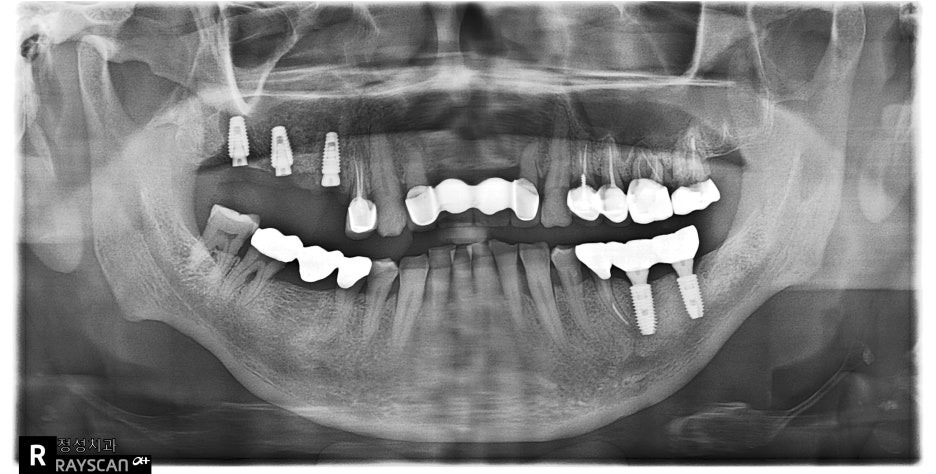

[ 치료 전 ]

왼쪽 구강 사진을 보시면 오른쪽 어금니에 치아가 발치된 공간에 잇몸이 많이 꺼져있고

엑스레이를 보시면 상악동 가운데 부분이 내려와있어서 뼈가 부족한 부분이 보입니다.

임플란트는 어금니에 7~10mm정도의 길이를 보통 식립하게 되는데요.

지금은 부족한 부분에는 3mm정도밖에 뼈가 없어서 골이식이 필요해보입니다.